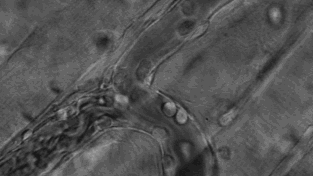

免疫細胞可穿過血管壁奔赴“戰(zhàn)場”

免疫細胞在反抗和吞噬癌細胞